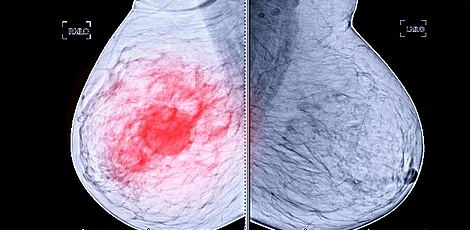

오늘은 유방암 초기 증상에 대해 살펴보겠습니다. 유방암은 가슴에 발생한 암을 의미합니다. 유방암 진단을 받는 환자의 수는 한 해 동안 2만 명에 달하고, 여성들한테 제일 흔한 암 중 하나입니다. 2019년 이전까지 1위였던 갑상선암을 넘어 유방암이 여성 암 유발률 1위에 올랐습니다. 가슴에 응어리(멍울)가 만져지고 진통이 생기게 되면 어쩌면 유방암 초기 증상일 수 있습니다.

유방암은 유방조직에 악성 세포 암이 발생하는 것을 의미합니다. 유방조직이 적은 남자 또한 유방암에 걸릴 수 있습니다.

유방암 초기 증상으로 응어리나 멍울이 만져지면 유방암 초기 증상을 의심해보아야 합니다. 가슴이나 겨드랑이 방향을 손으로 만졌을 경우 울퉁불퉁한 혹이 느껴진다면 의심해 보아야 합니다. 악성 종양인 경우 일반적으로 단단하고 고정되어 이동하지 않고 모양이 불규칙합니다. 하지만 멍울은 유선 내에 있는 혹으로, 90%가 양성 진단을 받는 것으로 알려져 있습니다. 이러한 응어리 멍울은 유방암과 관계없는 섬유선종이나 섬유낭종일 가능성도 높아 의료기관에서 정확히 진찰받는 것이 좋습니다.